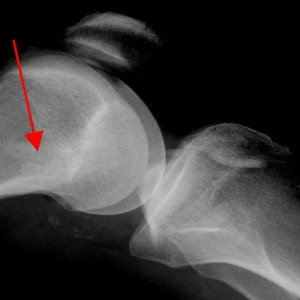

Анкеры для артроскопии плеча

В качестве расходных материалов для восстановления мягких тканей у Richard Wolf GmbH есть стерильные самонарезающие титановые анкеры для суставной губы гленоида и вращательной манжеты плеча.

- Имеются как титановые анкера для рефиксации суставной губы гленоида

- Так и для восстановления вращательной манжеты плеча